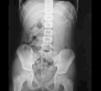

Se solicita un hemograma en el que se aprecia leucocitosis (12,51 × 103/μl) con marcada neutrofilia (92 %) y láctico deshidrogenasa (LDH) discretamente elevada (510 U/l). El resto de la bioquímica y la coagulación es normal. También se solicita una radiografía simple abdominal en decúbito supino (fig. 1).

Figura 1. Radiografía simple de abdomen.

En la radiografía de abdomen se observan imágenes de densidad cálcica en hipogastrio compatibles con dientes, por lo que se realiza una ecografía abdominal que muestra un ovario derecho de 42,3 mm con hiperecogenicidad de densidad cálcica compatible con teratoma; el resto es normal.

El diagnóstico de sospecha puede establecerse mediante radiografía simple de abdomen. En un alto porcentaje de casos (60-70 %)4 se encuentran calcificaciones o zonas de osificación en la parte inferior del abdomen. La presencia de dientes no es tan frecuente (20-30 %), pero permite realizar el diagnóstico específico. La ecografía es el método diagnóstico más sensible e inocuo5. Los signos típicos que se observan son: masa con refuerzo posterior por material sebáceo y pelo y bandas delgadas (pelos) en una cavidad quística. Por último, los marcadores tumorales son útiles por su gran sensibilidad y especificidad en medir la presencia de componentes histológicos, ya que estos tumores suelen estar asociados con actividad hormonal. Los más utilizados son: β -HCG, α-fetoproteína y CEA.

La conclusión principal es que ante un dolor abdominal agudo en niñas, la radiografía simple de abdomen tiene gran importancia para el diagnóstico.